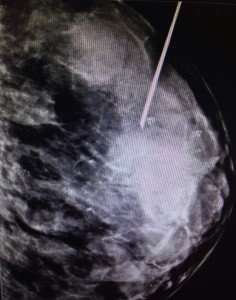

El procedimiento fue una biopsia radio quirúrgica de mama. Este tipo de cirugía se realiza para las lesiones no palpables de la mama. “Consiste en extraer una lesión que no se toca, con la ayuda del imagenólogo (especialista que maneja el mamografo) para poder guiar la operación. Con la guía de la mamografía se inyecta una marca de carbón líquido de un mililitro para buscar esa marca en el sitio preciso donde se encuentra la lesión”, explicó Cohen Imach.